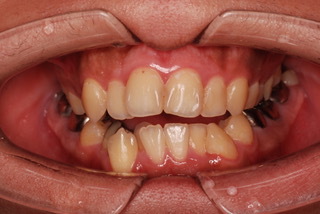

当院で行われた症例です。

下図の正面と横から見た前歯をご覧ください。

完全に前歯が開いてしまっていますね。